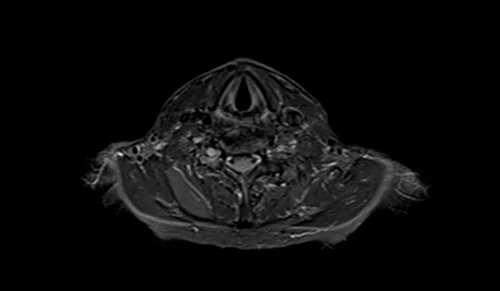

MRI brachial plexus axial STIR images